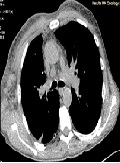

A Combination of Hodgkin's Lymphoma and Tuberculosis occurred with Bilateral Malignant Pleural Effusions

Daniel Valchev*, Mitko Mitev, Evelin Obretenov, Dimitar Kostadinov, Danail Petrov